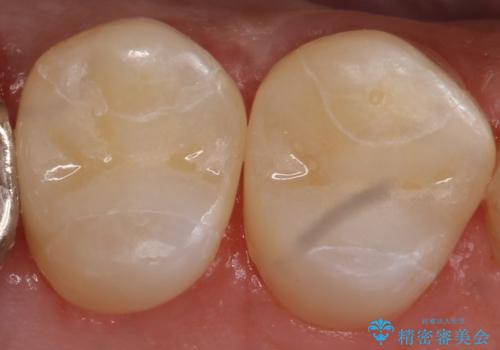

銀の詰め物を除去し、残った歯の量が多かったためセラミックインレーでの修復となりました。

歯の内側に詰めるインレーでの修復でも、形によっては外から見える場合があります。

適合の良いセラミックインレーにやり替えることで外から見た時の違和感がなくなります。

また今回は治療前の写真で食べ物が詰まっている様子が伺えますが、適合がよく段差のない修復をすることで食べ物が詰まることを減らし、結果的に虫歯のリスクを下げることも期待できます。